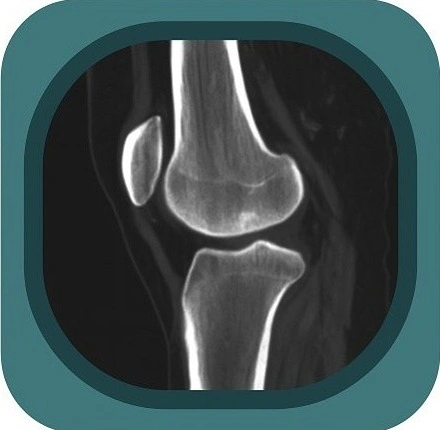

Explore full-body CT anatomy in 3 planes. Our high-resolution, carefully labelled images reveal micro-anatomy—ideal for radiologists, radiographers and surgeons.